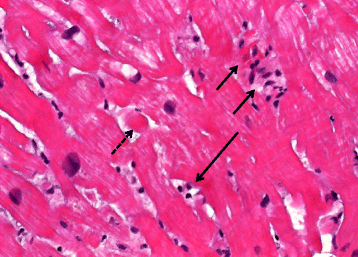

Fig. 1

Histologic presentation of case 1. Endomyocardial biopsy shows interstitial fibrosis with some interstitial lymphocytes. Signs of hypertrophy are detectable